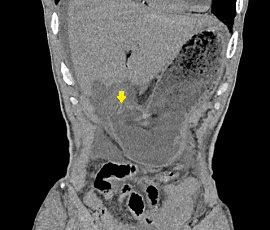

[十二指腸潰瘍穿孔] 手術:腹腔鏡下胃・十二指腸潰瘍穿孔縫合術

CT画像